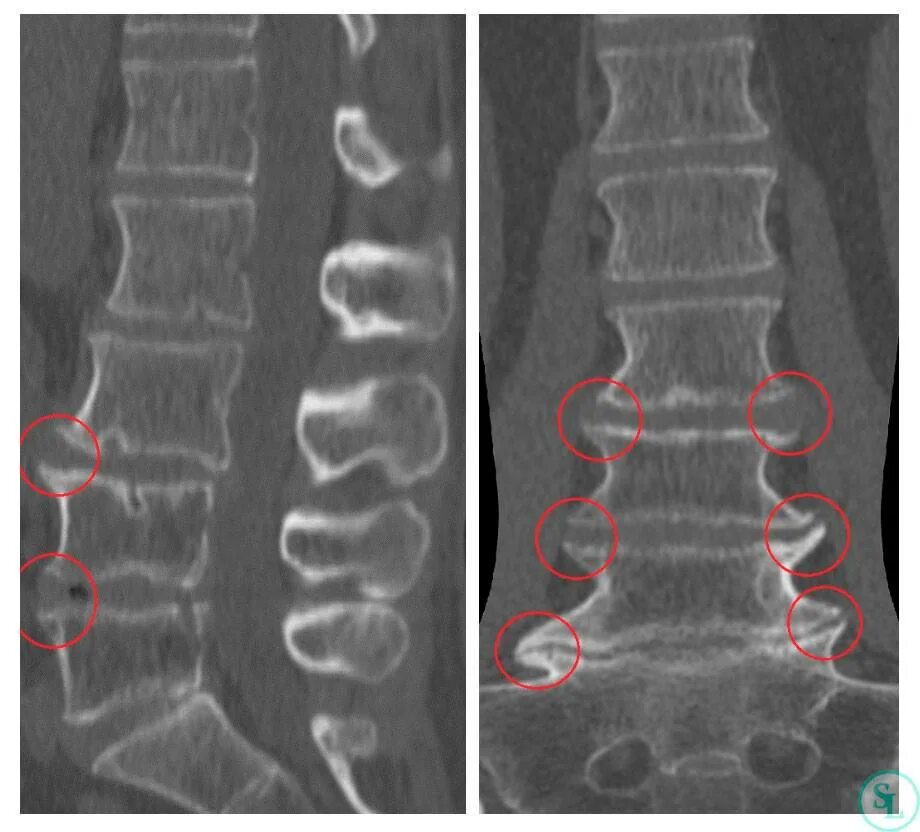

Деформирующий спондилез кт. спондилёз грудного отдела позвоночника на кт. деформирующий спондилез поясничного отдела l1 s1. l1-l4 деформирующий спондилез.

Спондилёз поясничного отдела позвоночника на кт. спондилез пояснично-крестцового отдела позвоночника. остеофиты шейного отдела позвоночника. артроз дугоотросчатых суставов поясничного отдела.

Спондилёз пояснично-крестцового отдела l1 l2. спондилёз шейного отдела позвоночника рентген. спондилёз поясничного отдела позвоночника на кт. спондилез поясничного отдела рентген.

Спондилез с6-с7 что это. деформирующий спондилез позвоночника. спондилёз поясничного отдела позвоночника на кт. деформирующий спондилез грудного отдела позвоночника рентген.

Деформирующий спондилез шейного отдела рентген. деформирующий спондилез рентген. спондилёз поясничного отдела позвоночника на кт. спондилоартроз пояснично-крестцового отдела позвоночника кт.